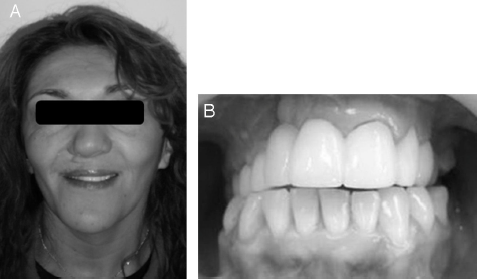

El plan de tratamiento consideró una prótesis fija plural que abarcara la mayoría de las piezas dentarias superiores con el fin de mejorar la estética y obturar la zona de la fístula buconasal ubicada a nivel del reborde alveolar. Para ello se realizó cirugía plástica periodontal en la zona debido a una hiperplasia gingival, y se corrigió mediante sistema perno-muñón la inclinación de los dientes 1.5 y 1.4. A través de esta prótesis fija plural se mejoró la estabilidad oclusal al transformar la mordida cruzada bilateral en una mordida vis a vis, se obturó la comunicación ubicada a nivel del diente 1.2 y se transformó la arcada dentaria de una fuerte forma triangular a forma semicircular, mejorando notoriamente la estética de la sonrisa (fig. 4).

A. Fotografía extraoral. B. Fotografía intraoral. Se observa prótesis fija plural desde diente 1.6 a 2.5, con mejora en la forma de la arcada, mordida vis a vis en sectores posteriores y armonía en la sonrisa